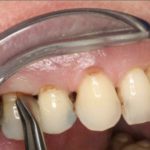

Верхушечный тип обычно не предполагает удаление зуба. Основная цель в данном случае – ликвидировать очаг воспаления, предотвратив заражение соседних зубов. Лечение каналов периодонтита сводится к удалению гноя или серозного образования в зубном канале, обработке антисептиком. В пораженный участок вводится турунда – марлевый тампон, смоченный лекарством. Канал закрывают временной пломбой, оставляют на 1-3 дня. После этого проверяют результат лечения, после чего назначают лекарства, мази, пасты при периодонтите для поддерживающей терапии, ускоряющие заживление.

Во время сильного воспаления сначала освобождают каналы от содержимого. Для этого применяют дренаж через десну, корневые каналы или лунку, если зуб был удален. Если апикальный периодонтит локализован глубже, разрезают переходную складку. Обычно этот метод применяется при абсцессе, которое является одним из осложнений заболевания. Все манипуляции осуществляют под местным обезболиванием, чтобы добраться до пораженного участка без причинения дискомфорта пациенту.